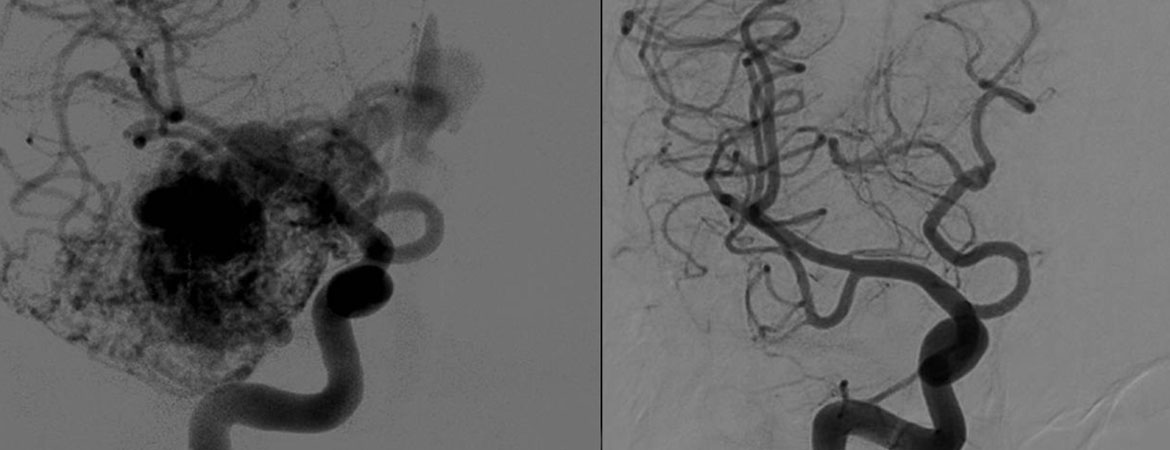

Arteriovenous malformations (AVMs) are a type of vascular malformation characterised by an abnormal connection between arteries and veins, bypassing the capillary system. This absence of capillaries generates an elevated pressure (hyperdebit), in both the AVM and the venous drainage, increasing the risk of rupture. Management modalities are: observation, microsurgical clipping, endovascular treatment and radiosurgery. The former can be used alone or in the frame of a multidisciplinary approach. We review our single-institution experience with gamma knife radiosurgery (GKR) over a period of 5 years.

The study was open-label, prospective and nonrandomised. Fifty-seven consecutive patients, benefitting from 64 GKR treatments, were included. All were treated with Leksell Gamma Knife Perfexion (Elekta Instruments, AB, Sweden) between July 2010 and August 2015. All underwent stereotactic multimodal imaging: standard digital subtraction angiography, magnetic resonance imaging and computed tomography angiography. We report obliteration rates, radiation-induced complications and haemorrhages during follow-up course.

The mean age was 46 years (range 13–79 years). The mean follow-up period was 36.4 months (median 38, range 12–75 months). Most common pretherapeutic clinical presentation was haemorrhage (50%). The most common Pollock-Flickinger score was between 1.01 and 1.5 (46%) and Spetzler-Martin grade III (46%). In 39 (60.1%) of cases, GKR was performed as upfront therapeutic option. The mean gross target volume (GTV) was 2.3 ml (median 1.2, range 0.03–11.3 ml). Mean marginal dose was 22.4 Gy (median 24, range 18–24 Gy). The mean prescription isodose volume (PIV) was 2.9 ml (median 1.8, range 0.065–14.6 ml). The overall obliteration rates (all treatments combined) at 12, 24, 36, 48 and 60 months were 4.8, 16.9%, 37.4, 63.6 and 78.4%, respectively. The main predictive factors for complete obliteration were: higher mean marginal dose (23.3 vs 21.0 Gy), lower GTV (mean 1.5 vs 3.5 ml) and absence of previous embolisation (at 60 months 61.8% prior embolisation compared with 82.4% without prior embolisation) (for all p <0.05). Eight (14%) patients experienced complications after GKR. Overall definitive morbidity rate was 3.1%. No patient died from causes related to GKR. However, during the obliteration period, one case of extremely rare fatal haemorrhage occurred.

CONCLUSION

Radiosurgery is a safe and effective treatment modality for intracranial AVMs in selected cases. It can be used as upfront therapy or in the frame of a combined management. Obliteration rates are high, with minimal morbidity. The treatment effect is progressive and subsequent and regular clinical and radiological follow-up is needed to evaluate this effect.